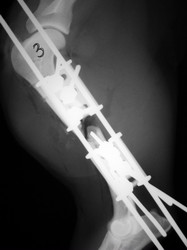

PRÁCTICAS CURSO DE FIJACIÓN EXTERNA PERFECCIONAMIENTO.

Húmero.